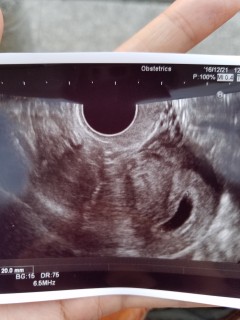

前回初めての妊娠は染色体の異常で初期流産をしました。そして今回またすぐ妊娠。検査薬をして間を空けて診察に行こうと思いましたが茶おりが出たので早めの受診。初妊娠の時より確実に大きい胎嚢確認できました。GS19.1mm 次は2週間後、ドキドキ

前回受診した時の5週0日(9mm)から今回5週5日(2cm)胎嚢が約二倍の大きさになりました。卵黄嚢や胎芽がみれるかなと少し期待してましたが……まだ見えませんでした。。2週間後の確認までドキドキです!